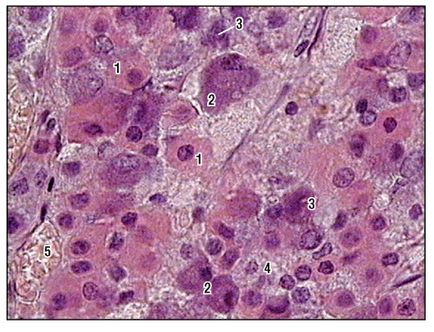

Fig. 166. Parte periferică a glandei pituitare (fragment) (colorată cu healon, creștere mare):

1 - celulă acidofilă; 2 - celule bazofile (cu macula), gonadotropocite; 3 - celulă bazofilă (fără macula), tirotropocit; 4 - celule cromofobe; 5 - capilare sinusoidale